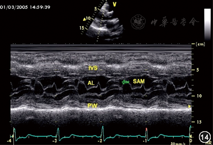

| 左心室 | 常用于测量左心室内径和射血分数,正常值和常见异常同二维超声(图13) | 左心室流出道梗阻时SAM征(图14) | 舒张末期测量内膜至内膜的垂直距离,取样线置于二尖瓣瓣尖水平并垂直于室壁,当心尖上翘取样线不能垂直于室壁时,不能采用此方法 | ||

| SAM征的出现提示有左心室流出道梗阻,但并不一定是器质性的,也可为血容量不足引起的动力性梗阻 | |||||

注:SAM(systolic anterior motion)征 二尖瓣前叶收缩期前移现象